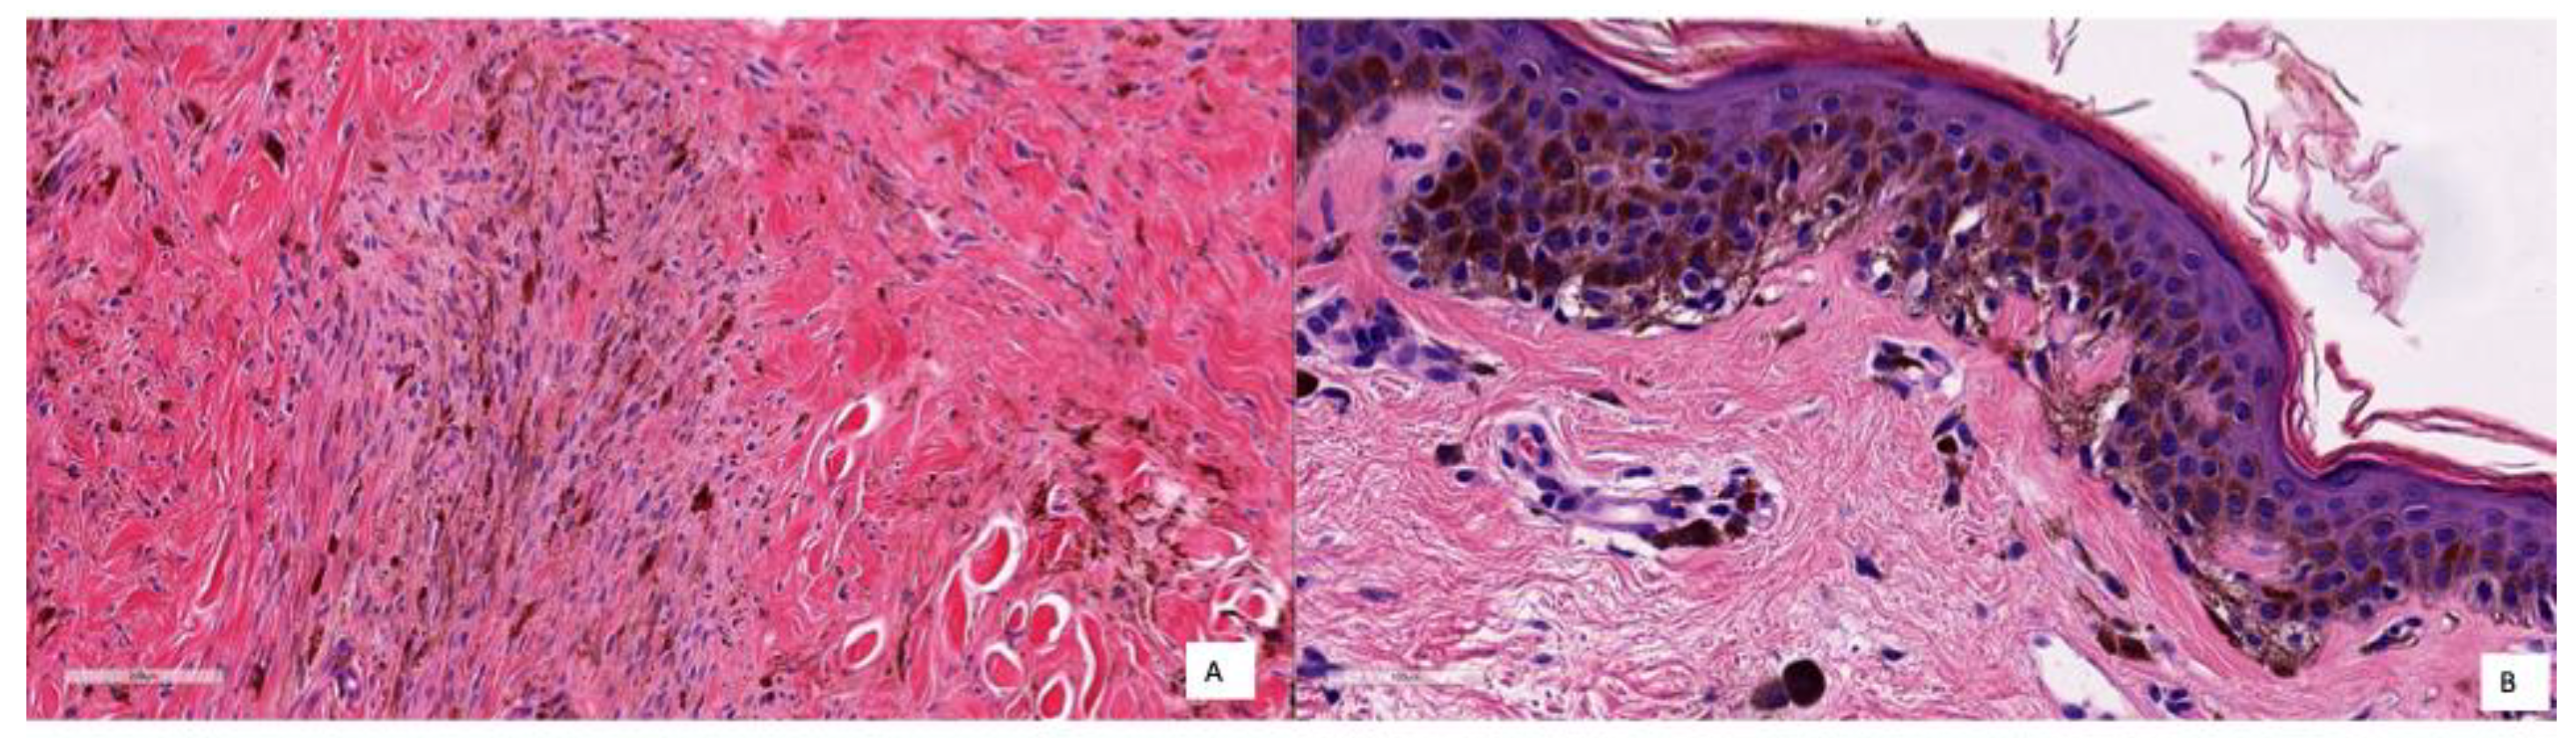

Finally, to quantitatively evaluate the quality of our model classification, we tested the performance of our classifier by comparing it to the diagnosis made by two histopathologists (as determined with all methods and information at hand) with the test set. The physicians who performed the evaluation are MGR, CPV and JLRP, who are expert dermatopathologists in the field and assigned the class labels. Diagnosis of melanocytic lesions is based on histopathological criteria, including asymmetry, cytological atypia, maturation, pagetoid extension, mitosis and dusty pigmentation in melanocytes, which the pathologist uses to classify these lesions as benign or malignant and to establish a specific diagnosis. Since these features may become ambiguous in some cases, expertise is most valuable in others. However, our strikingly accurate models (KNN and RF models) yielded 100% sensitivity and 95.55% specificity for the KNN classifier and 97.7% for the RF model, which means two cases were FPs with the KNN model and only one with the RF model. Coincidentally, both model fails to classify the same case (a deep blue nevus) as benign. The histopathological features of the two false-positive cases are compiled in Table 6. The values range from 1 to 3, which means: 1 feature is fulfilled by nothing or very little, 2 features are fulfilled in some way, and 3 features are fulfilled by a lot or completely. In some cases, this value is NA (Not Available).

If we describe these two cases in detail, the first was a deep blue nevus showing a proliferation of spindled pigmented melanocytes in the deep reticular dermis. In the second case, there was a basal proliferation of pigmented melanocytes. These cases are difficult to classify even for physicians, as they share common characteristics with both nevi and melanoma. Therefore, it is understandable that the model could misclassify them. A potential solution to this problem is to increase the number of similar cases in the dataset, which could help improve the model’s ability to distinguish between these challenging examples.

To better illustrate how the model diagnoses, different pictures of the cases corresponding respectively to TNs, TPs and FPs are shown in Figure 8, Figure 9 and Figure 10. Figure 8 shows several examples of TN cases, including a case of dermal melanocytic nevus (Figure 8A), a Reed nevus (Figure 8B), a Spitz nevus (Figure 8C) and a dysplastic nevus (Figure 8D). Figure 9 shows two examples of True Positive (TP) cases, including a spreading superficial melanoma of 3.79mm of Breslow thickness with balloon degeneration (case A) and a superficial spreading melanoma, ulcerated of 5.5 mm of Breslow thickness (case B).

As said earlier, only two cases were classified as FP with the KNN model and only one with the RF model. Coincidentally, both models failed to classify the same case (a deep blue nevus) as benign. The histopathological features of the two FP cases are compiled in Table 5, and the images are shown in Figure 10. In Case A, the deep infiltration of the pigmented melanocytes and the spindled shape may be misinterpreted; in Case B, there is a basal proliferation of pigmented melanocytes.